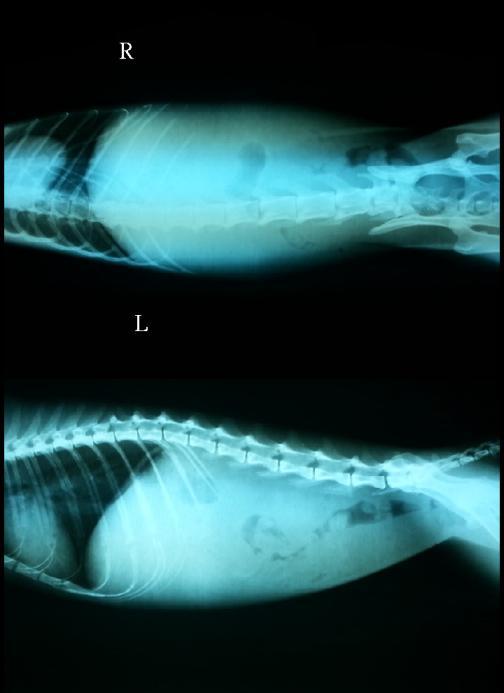

主題: 戰勝命運多舛的白底虎斑貓~已痊癒 申請者姓名: 張慧敏 花色: 申請日期: 2012-11-22 01:01:39 申請者部落格: 申請者臉書網址: 所在縣市/合作醫院: 台北市/澄毅動物醫院 治療費用: 62570元 需求人數: 63人 已結案 (2013-06-27 14:04:39) 報名人員: Choco Chen(已付款)、Rebecca Wu(已付款)、Apple Chen(已付款)、Q比(已付款)、momo(已付款)、cooljojo1015(已付款)、張懿茹(已付款)、misselaine(已付款)、Kit Mimicat(已付款)、Grace Luo(已付款)、Pei Shuan Ni(已付款)、chiawei(已付款)、香香(已付款)、Freesia Tsai(已付款)、小心心(已付款)、April(已付款)、周星星(已付款)、波波(已付款)、席小敬(已付款)、Ping Meng(已付款)、Michelle(已付款)、Sky(已付款)、Sky(已付款)、Sky(已付款)、Sky(已付款)、Sky(已付款)、Sky(已付款)、Sky(已付款)、Sky(已付款)、Sky(已付款)、Sky(已付款)、Sky(已付款)、Sky(已付款)、Sky(已付款)、Sky(已付款)、Sky(已付款)、Sky(已付款)、Sky(已付款)、Sky(已付款)、Sky(已付款)、Sky(已付款)、Sky(已付款)、Sky(已付款)、Sky(已付款)、Sky(已付款)、Sky(已付款)、Sky(已付款)、Sky(已付款)、Sky(已付款)、Sky(已付款)、Sky(已付款)、Sky(已付款)、Sky(已付款)、Sky(已付款)、Sky(已付款)、Sky(已付款)、Sky(已付款)、Sky(已付款)、Sky(已付款)、Sky(已付款)、Sky(已付款)、Sky(已付款)、Sky(已付款)、 候補人員: 動物病情說明: 牠平常在新店安康路二段附近出沒,因個性好,所以在TNR後考慮送養,但在平溪張媽媽保育場中卻出現嘔吐不吃及拉肚子,緊急送醫。

檢查後發現嚴重的牙結石及牙齦發炎,建議全口拔牙手術。

但在驗血中發現嚴重貧血、黃疸指數太高、營養不良,血液抹片中發現疑似血液寄生蟲。胰臟炎、愛滋白血及梨型鞭毛蟲都是陰性,醫師建議貧血狀況改善後再進行拔牙手術。

住院後第三天出現呼吸道疾病,讓原本問題更加複雜。

在住院期間中,經由鼻胃管強迫灌、點滴及藥物治療後,貧血問題一直沒有改善。期間因為貧血太嚴重,由醫院的店貓緊急捐血才維持住貧血,之後又接受第二次捐血後,病情才慢慢有改善,也順利接受全口拔牙手術,確定能自己進食後,帶回平溪張媽保育場照顧。

因為保育場內還有很多的狗貓需要照顧,張媽媽一直期待撐過這場大病的牠能趕快找個好人家好好照顧牠。但64天的住院中,因為有輸血、灌食及定期的血檢追蹤貧血,所以醫療費也相對較高。